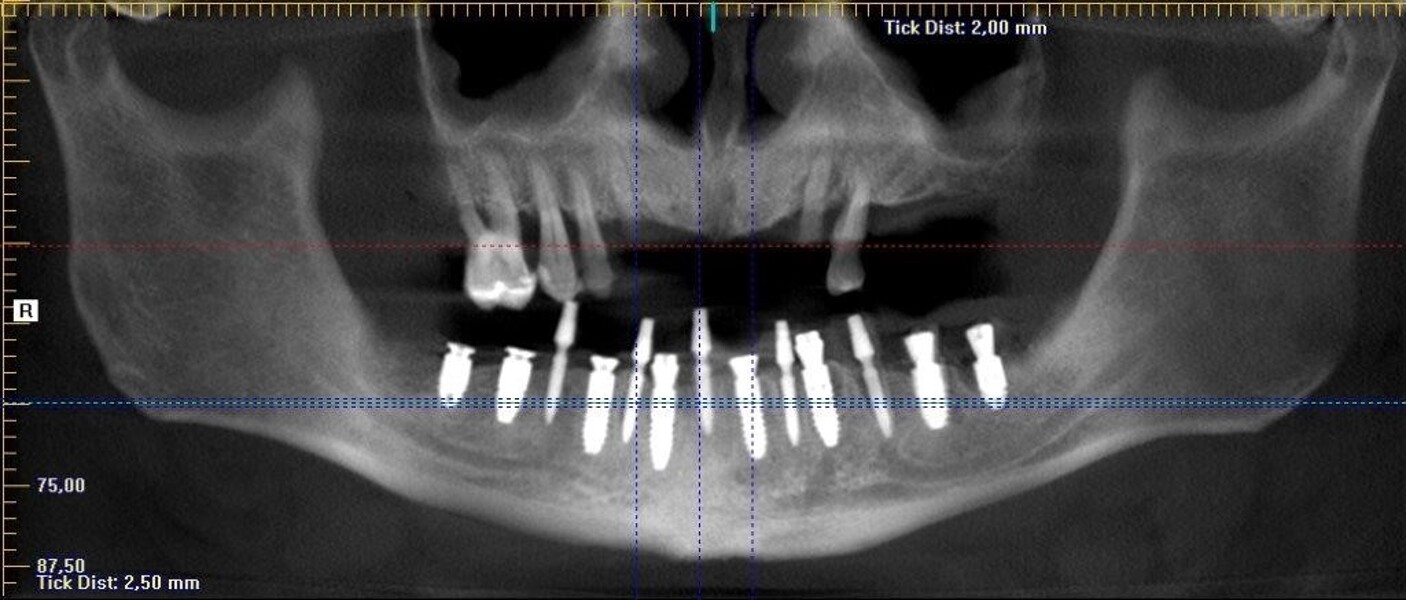

Implantacja z wykorzystaniem szablonu nawigacyjnego 3D